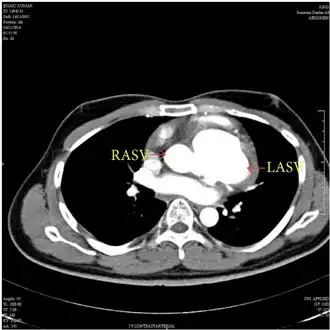

MDCT aortogram suggested left aneurysm of sinus of Valsalva and right aneurysm of sinus of Valsalva with extension into the interventricular septum.

The first step in diagnosis is typically transthoracic echocardiography. However, if surgery is planned or if the standard echocardiogram lacks sufficient detail, then one or more additional studies are recommended. These studies include transesophageal echocardiography, 3D echocardiography, CT Angiography and aortic angiography.[4] Cardiac MRI may be another option.[2]